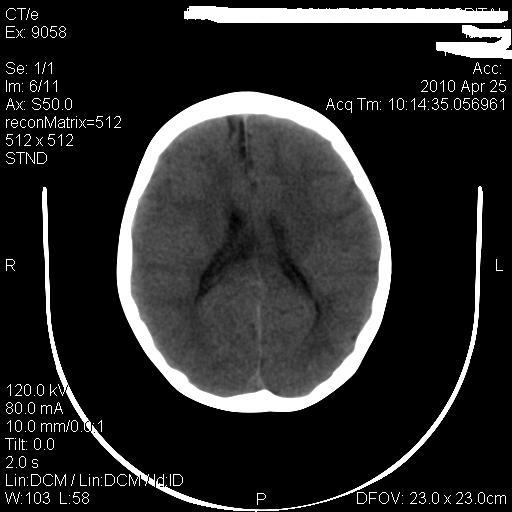

标题: PED3218:3岁女孩,曾有外伤史。未提供前片 [打印本页]

标题: PED3218:3岁女孩,曾有外伤史。未提供前片

发育略有障碍。欢迎大家发言。谢谢!

考虑右侧额顶叶脑软化灶并脑穿通畸形。

考虑:1)右侧额顶叶脑软化灶并脑穿通畸形。2)胼胝体发育不良。

支持考虑:1)右侧额顶叶脑软化灶并脑穿通畸形。2)胼胝体发育不良。

1)右侧额顶叶脑软化灶。2)胼胝体发育不良?

考虑右侧额顶叶软化灶并脑穿通畸形,胼胝体发育不全。

还有脑室周围白质软化症